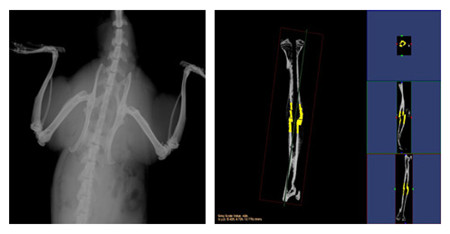

小動物CT服務通過采用錐形X線束,不僅能夠獲得真正各向同性的容積圖像,提高空間分辨率,提高射線利用率,而且在采集相同3D圖像時速度遠遠快于扇形束CT。可以對不脫鈣骨骼和動物牙齒進行microCT檢測服務,分析其內部結構和提供給您高清晰、高質量的掃描圖像。活體研究對象通常為小鼠、大鼠或兔等活體小動物,可以實現生理代謝功能的縱向研究,顯著減少動物試驗所需的動物數量;離體研究對象通常為離體標本(例如骨骼、牙齒)或各種材質的樣品,可分析其內部結構和力學特性。

操作簡單、影像系統性能強大,確保真正的容積透視和精確定量;集成的系統結構設計使從動物放置到數據分析與保存這一整套工作流程更高效。

結果示意圖:

小動物CT結果示意圖小動物CT結果示意圖